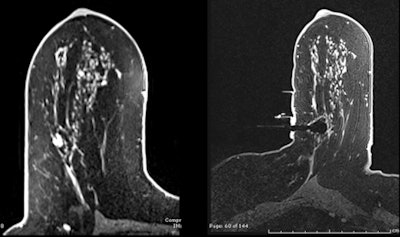

| Above, normal screening mammogram of contralateral right breast in patient with newly diagnosed left breast cancer and "not dense" breast tissue. Below, MRI reveals suspicious mammographically occult mass in right breast; MRI-guided biopsy yields diagnosis of contralateral infiltrating ductal carcinoma. All images courtesy of Dr. Reni Butler. |